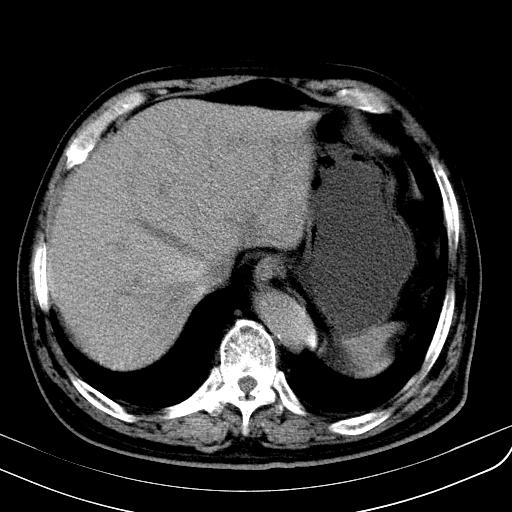

胃底靠近胃大弯处可见一圆形软组织影,直径为3.45cm,ct值约为30.1hu

考虑胃底平滑肌瘤。血肿不除外。